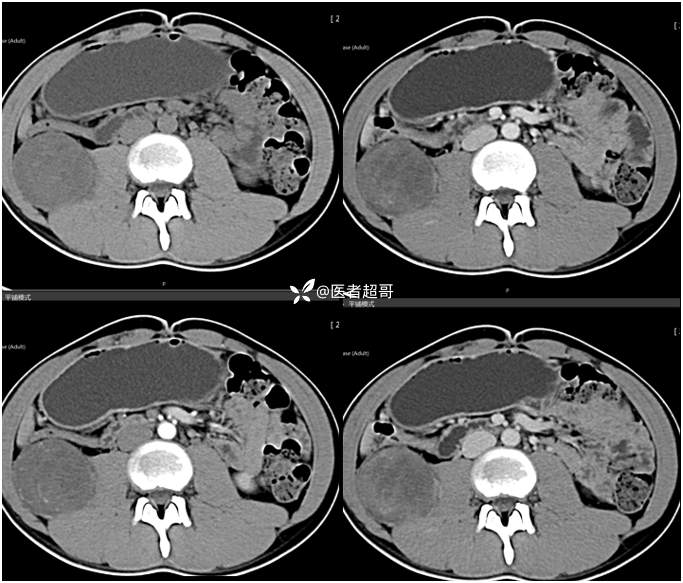

【影诊笔记754】腰痛就诊,腹膜后实性占位,请诊断分析!

主 诉:腰痛2月。

现病史:患者2月前无明显诱因出现腰背部疼痛,夜间为著。患者无头痛、头晕,无恶心、呕吐,无胸闷、憋气,无腹痛、腹胀。无尿频、尿急、尿痛等现象。患者在院外未作特殊治疗。为求进一步诊疗,来我院肾内科门诊就诊。门诊行双肾、输尿管、膀胱(前列腺)彩超提示:腹膜后实性占位。患者遂来我科就诊。我科以“腰痛”收治入院,患者自发病以来,神志清,精神可,饮食可,睡眠差。小便如上述,大便未见明显异常。体重无明显增减。